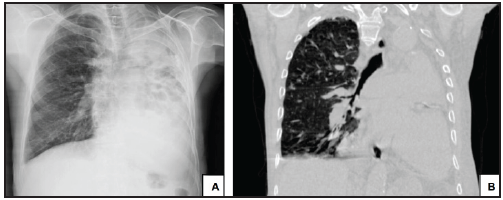

Masculino de 69 años de edad hipertenso, con falla cardiaca FEVI 50%, enfermedad pulmonar obstructiva crónica oxigenorrequiriente, tabaquismo IB 350 y tuberculosis pulmonar tratada; ingreso a urgencias por disnea MRCm 4/4, tos con expectoración amarilla y fiebre no cuantificada; disminución de ruidos respiratorios. Radiografía de tórax con radiopacidad difusa heterogénea en hemitórax izquierdo y en TC de alta resolución se demostró fibrotórax izquierdo.

Figura 1 A. Radiografía de tórax en proyección P-A. Evidencia radiopacidad difusa heterogénea del hemitorax izquierdo asociada perdida de volumen ipsilateral. B. Proyección coronal de TC de alta resolución en ventana para pulmón que evidencia pérdida de volumen del pulmón izquierdo con consolidación y bronquiectasias varicosas.